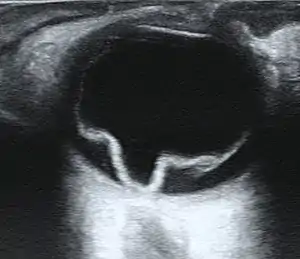

| Ultrasound of a retinal detachment in a patient presenting with complete vision loss and light perception only. | |

Ultrasound, MRI, and CT scan are commonly used to diagnose retinal detachment.